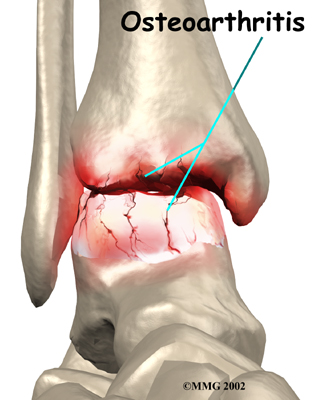

Inside the joint, the bones are covered with a slick, smooth material called articular cartilage. Articular cartilage is the material that allows the bones to move against one another in the joints of the body. The cartilage lining is about one-quarter of an inch thick in most joints that carry body weight, such as the ankle, hip, or knee. It is soft enough to allow for shock absorption but tough enough to last a lifetime, as long as it is not injured.

Injury to a joint, such as a bad sprain or fracture, can cause damage to the articular cartilage. The cartilage can be bruised when too much pressure is exerted on it. This damages the cartilage, although if you look at the surface it may not appear to be any different. The injury to the material doesn't show up until months later. Sometimes the cartilage surface is damaged even more severely, and pieces of the cartilage are ripped from the bone. These pieces do not heal back and usually must be removed from the joint surgically. If not, they may float around in the joint, causing the joint to catch and be painful. These fragments of cartilage may also do more damage to the joint surface.

Once this cartilage is ripped away, it does not normally grow back. Unlike bone, holes in the surface are not simply replaced by the cartilage tissue around the hole. Instead the defects are filled with scar tissue. The scar tissue that forms is not nearly as good a material for covering joint surfaces as the cartilage it replaces. It just can't support weight and isn't smooth like true articular cartilage.

Over many years this imbalance in the joint mechanics can lead to damage to the articular surface. Since articular cartilage cannot heal itself very well, the damage adds up. Finally, the joint is no longer able to compensate for the increasing damage, and it begins to hurt. The damage occurs well before the pain begins.

Pain is the main problem with arthritis of any joint. This pain occurs at first only related to activity. Usually, once the activity gets underway there is not much pain, but after resting for several minutes the pain and stiffness increase. Later, when the condition worsens, pain may be present even at rest. The pain may interfere with sleep. The joint may swell, fill with fluid, and feel tight, especially following increased activity. As the articular cartilage starts to wear off the joint surface, the joint may squeak when moved. Doctors refer to this sound as crepitation.

When OA has reached a very severe stage, the bone itself under the articular cartilage may become worn away. This can lead to increasing deformities around the joint. In the final stages, the alignment of the bones can begin to form odd angles where they meet at the joint.